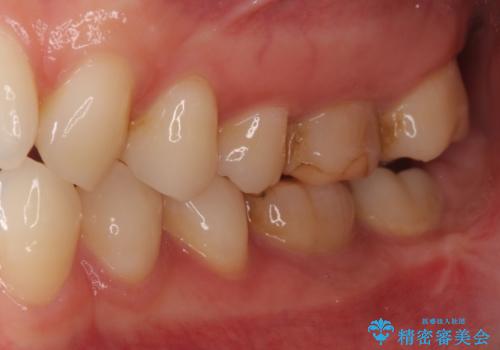

[20代女性]オールセラミッククラウン 根管治療後の補綴

![[20代女性]オールセラミッククラウン 根管治療後の補綴の症例 治療前](https://seimitsushinbi.jp/wp/wp-content/uploads/2019/09/IMG_9946-500x350.jpg)

![[20代女性]オールセラミッククラウン 根管治療後の補綴の症例 治療後](https://seimitsushinbi.jp/wp/wp-content/uploads/2019/09/IMG_9624-500x350.jpg)